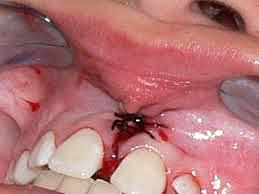

• Frenilectomía del frenillo labial superior

Frenilectomía del frenillo labial superior

Se realizará esta cirugía pre-protésica para poder tener un frente estético con las carillas directas que se colocaran posteriormente, está cirugía también ayudará que el frenillo labial no quede presionado con las restauraciones.